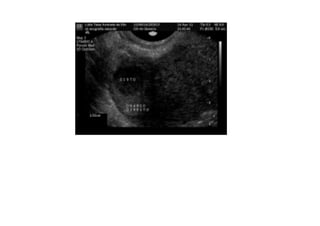

•  Examen  du  cas   d’une  pa=ente   traitée  pour  de   l’endométriose  par   chirurgie,  qui   con=nuait  a  avoir   une  conges=on   pelvienne.  L’examen   a  démontré  qu’elle   souffrait  également   de  varices   pelviennes.

Refluxo  de  veia  Gonadal  com  formação   varicosa  ao  lado  do  ovário